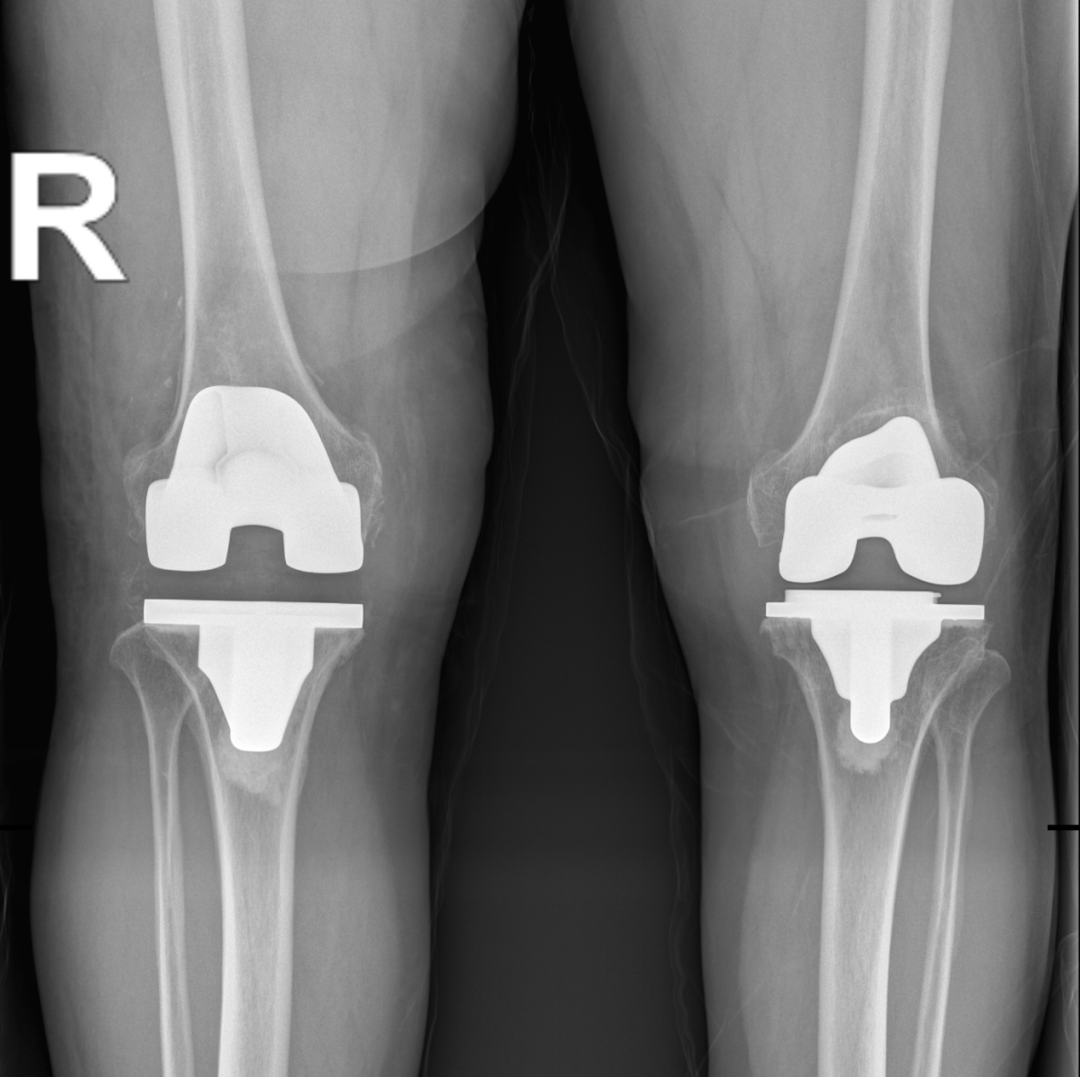

第二次右侧人工全膝关节置换术后

徐驰主任表示, 关节炎种类繁多,一般人难以准确辨别,如果关节炎发作,忍痛而不治疗往往对关节造成更大的破坏,加重关节炎的症状,增加致残的危险,出现关节疼痛和病变时建议早期去医院就诊,以免耽误病情,造成不可逆的损伤。